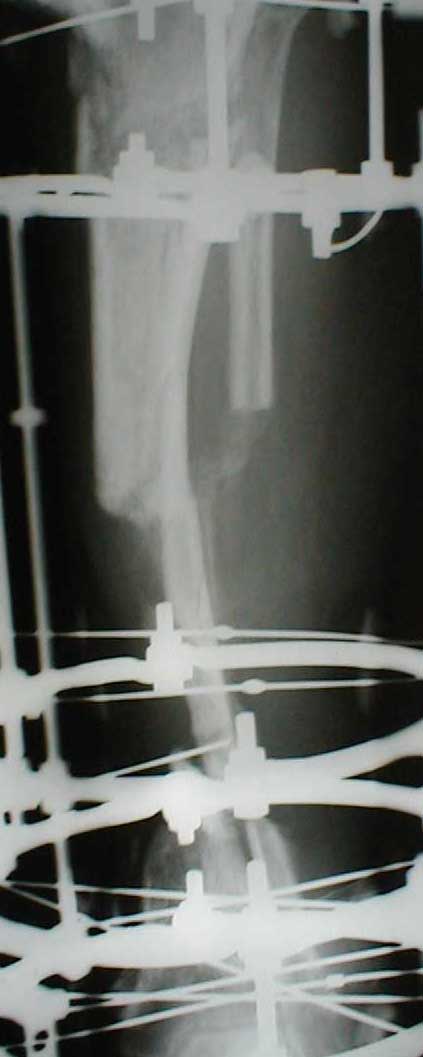

В приложении - моё наблюдение (возможно, уже представлял, тогда

извините).

Нога попала в пресс.

Ко мне больной попал черз 1,5-2 года после травмы и нескольких

операций с синегнойной инфекцией на всю голень. Меня пригласили на консультацию

насчет ампутации.

Лечил я его месяцев 8.

Малоберцовка полностью перестроилась, нога опороспособна.

При ходьбе на дальние расстояния пользуется тростью.

Осталась трофическая язва, периодически закрывается.

Клинические снимки где-то есть, но не очень качественные.

Один из вариантов.

С уважением Александр Артемьев